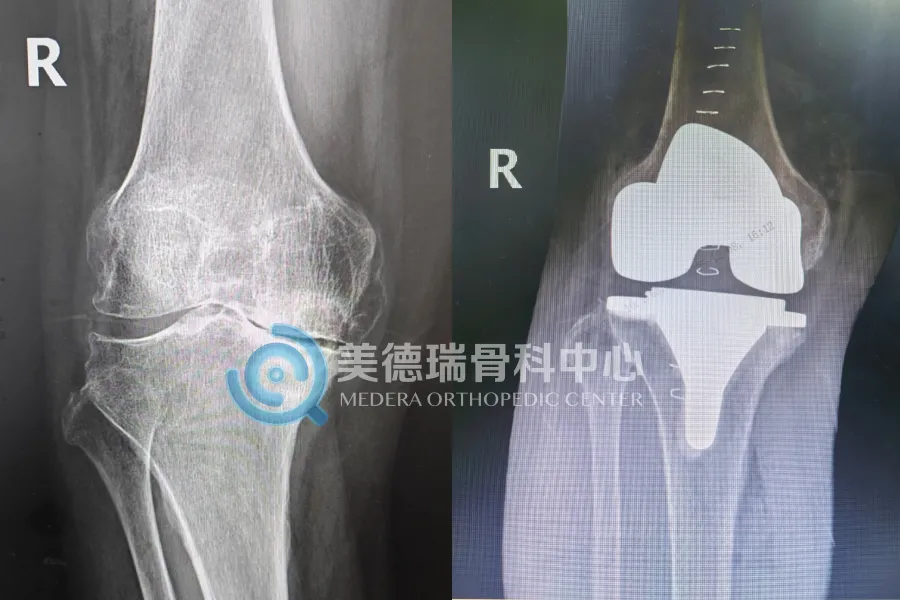

相比之下,70岁的郭女士病情则更为复杂。她的膝关节磨损已累及多个间室,结合严重的活动受限表现及影像结果,单纯的局部修补已无法解决问题。经过综合评估,团队为她制定了全膝关节置换术(TKA)方案,以彻底重建关节功能。